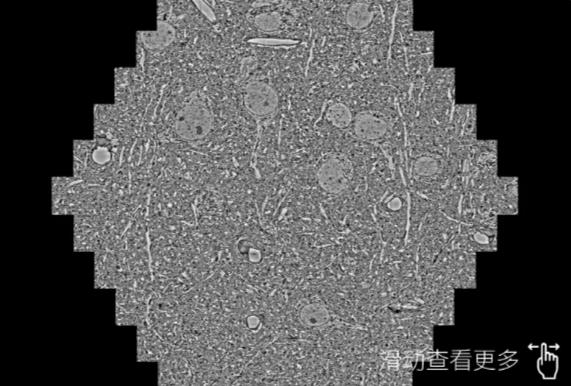

鼠脑切片。左图使用南川蔡司南川扫描电镜MultiSEM706对165μmx143pm面积区域成像,耗时仅需1.5秒。右图为鼠脑切片中30μm区域放大效果。样品由芝加哥大学B.Kasthuri提供。

使用蔡司高速南川扫描电镜MultiSEM对1mm²人脑皮层组织进行高分辨成像,并对其中的各种细胞结构进行三维重构分析。左图展示了2x3mm²组织平面中锥体神经元的三维重构效果。右图显示了局部体积神经元三维重构。图像由哈佛大学chtman实验室提供,渲染图由D. Berger 制作。